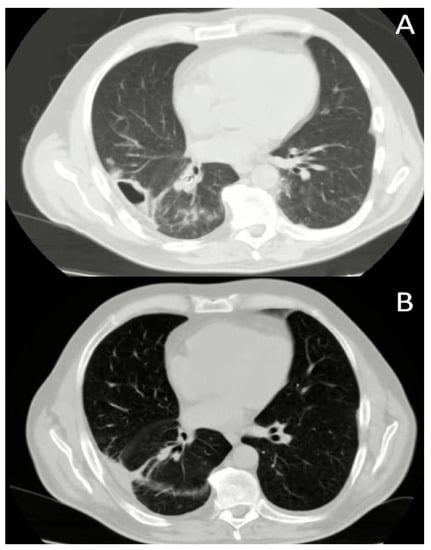

Endoscopic Treatment and Pulmonary Rehabilitation for Management of Lung Abscess in Elderly Lymphoma Patients